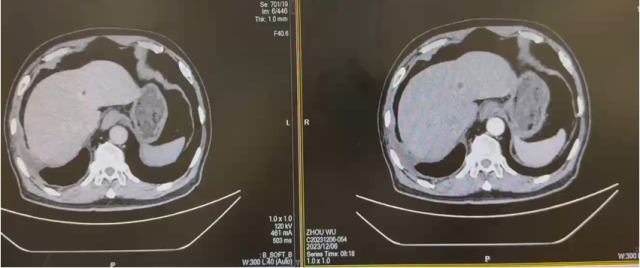

CT(2022.7):1. 右肺转移瘤切除术后改变;2. 左肾上腺结节,转移?3. 左肾多发结节,转移瘤?4. 腹膜后淋巴结肿大,转移可能;5. 左肾多发小囊肿。

CT(2023.7.17):1. 左肾上腺结节、左肾结节及肿块较前明显增大:转移?左肾 CA 并左肾内、肾上腺转移?2. 腹膜后淋巴结较前增大,转移可能;3. 余况基本同前。

CT(2023.12.6):1. 左肾上腺结节较前稍缩小、左肾结节及肿块较前稍缩小;2. 腹膜后淋巴结转移灶同前;3. 余况基本同前。

CT(2025.4.7):1. 左肾上腺肿块较前明显增大;2. 左肾结节及肿块部分较前增大;3. 腹膜后淋巴结同前;4. 右侧胸膜结节状增厚较前增大,建议追踪;5. 余双肺情况基本同前。